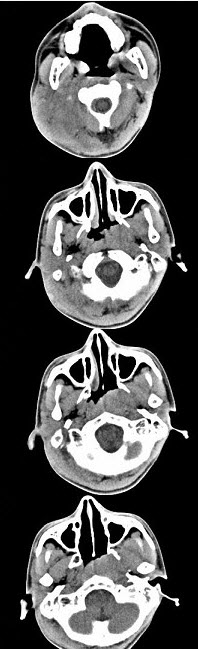

男,17岁,自诉鼻涕中带血3个月,伴耳闷、听力减退,无发热。如图所示鼻咽部病灶最可能的诊断为()。

A、咽旁脓肿

B、鼻咽部恶性淋巴瘤

C、鼻咽癌

D、小唾液腺混合瘤

E、鼻咽部淋巴组织增生

C